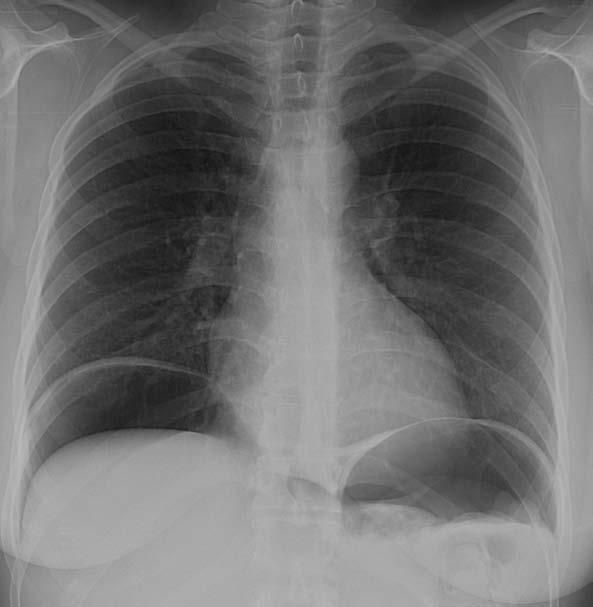

The patient's CT scan of the chest demonstrated small collections of gas in the mediastinum, consistent with pneumomediastinum (Figure 1). The chest radiograph showed a large amount of free air below both hemidiaphragms (Figure 2). Cardiac and mediastinal contours were within normal limits. The lungs were clear, and there was no pleural effusion.

Figure 1 – CT scan (lung windows) of the

upper thorax demonstrates small collections of

gas (arrows) in the mediastinum, consistent with pneumomediastinum.